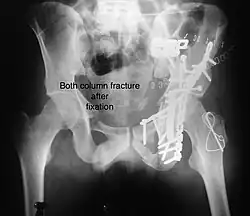

Both column fracture showing floating weight bearing dome -

Both column fracture after fixation with screws and plates -

Function after fixation both column fracture